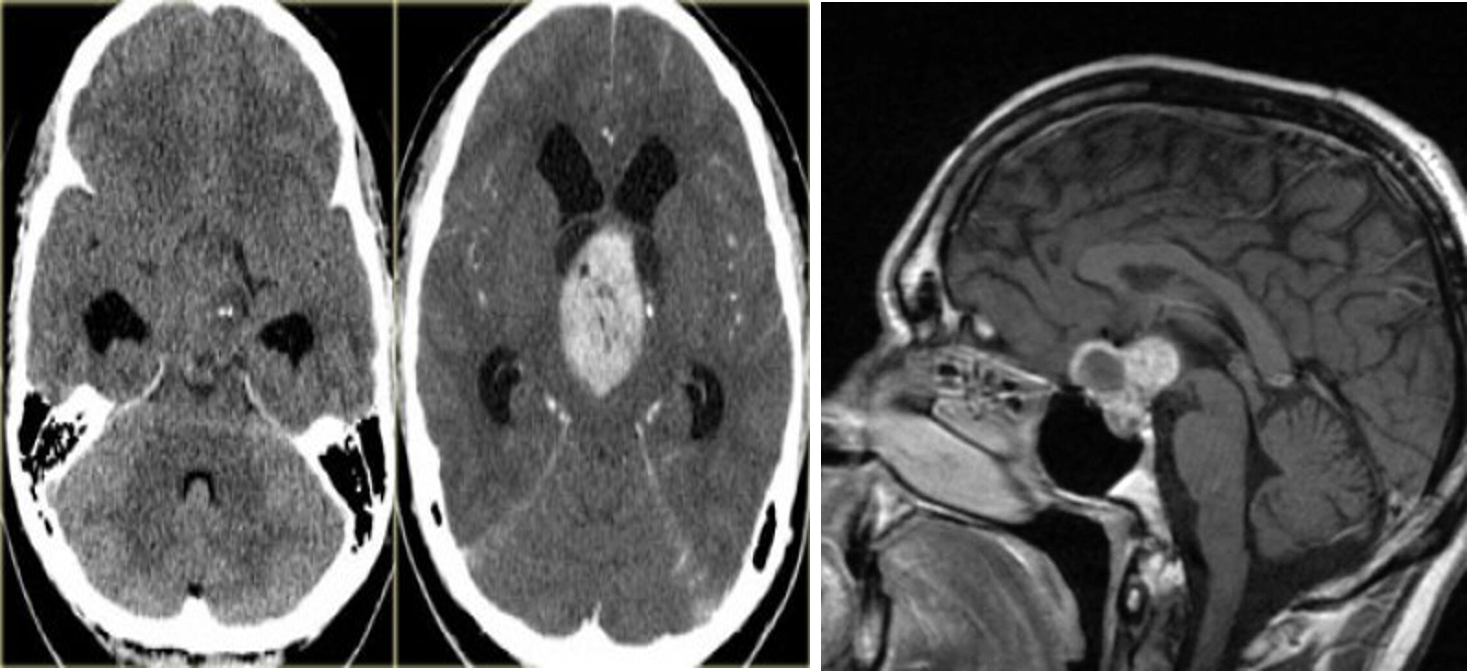

Imaging: Suprasellar calcified cyst with a lobulated contour

A,B) Craniopharyngioma pre and post contrast

C) MRI head (T1 weighted; with contrast; sagittal of a patient with acute visual loss in the right eye - There is an intrasellar and suprasellar mass with both cystic and solid portions. The solid portions show strong contrast enhancement.